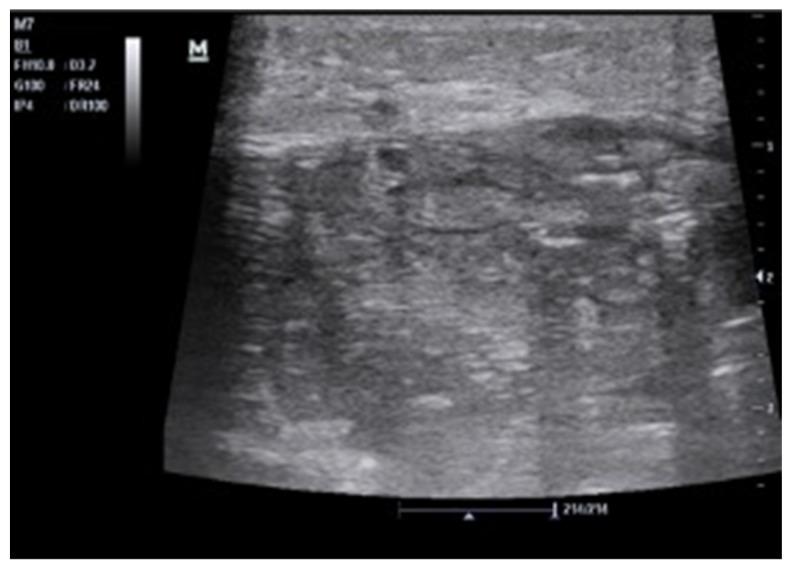

A key issue in abdominal US is the assessment of fluid, which is usually anechoic, thus appearing "black". Our approach focuses on searching for fluid in non-traumatic patients, providing a new, simplified method for point-of-care US (POCUS).

Fluid assessment is based on a three-step analysis that we can thus summarize. 1. Look for black where it should not be. This means searching for effusions or collections. 2. Check if black is too much. This means evaluating anatomical landmarks where fluid should normally be present but may be abnormally abundant. 3. Look for black that is not clearly black. This means evaluating fluid aspects, whether wholly anechoic or not (suggesting heterogeneous or corpusculated fluid).

腹部超声检查中的一个关键问题是对液体的评估,液体通常是无回声的,因此呈现“黑色”。我们的方法专注于在非创伤性患者中寻找液体,为床旁超声检查(POCUS)提供了一种新的、简化的方法。

液体评估基于我们可以总结的三步分析。1. 在不该出现黑色的地方寻找黑色。这意味着寻找积液或液性聚集。2. 检查黑色是否过多。这意味着评估正常情况下应该有液体但可能异常增多的解剖标志。3. 寻找并非明显黑色的黑色。这意味着评估液体的特征,无论是否完全无回声(提示液体不均匀或有细胞成分)。